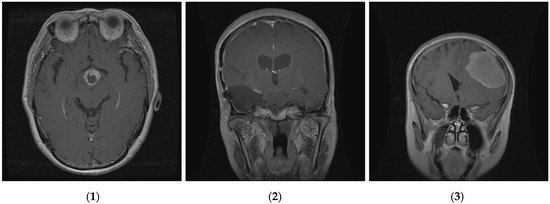

Figure 4.

Three classes of brain tumor datasets; (1) meningioma, (2) glioma, and (3) pituitary brain tumors.

The proposed method was examined and tested by using data on brain tumors gathered between 2005 and 2010 from Tianjin Medical University General Hospital and Nanfang Hospital in Guangzhou, Guangdong, China [59]. Three distinct types of brain tumors are represented in this brain tumor dataset, which consists of 3064 T1-weighted contrast-enhanced pictures from 233 patients: meningioma (708 slices), glioma (1426 slices), and pituitary tumor (930 slices). We randomly divided these images into two groups, using 80% for training and validation and 20% for testing the model. This means that the pituitary sample is divided into 744 slices to train the model and 186 slices for the test; the glioma sample is divided into 1141 slices for training and the remaining (285 slices) are used for the test; and the meningioma is divided into 566 slices for training the model and 142 slices for testing. The results are represented in Figure 3. The images are 512 × 512 pixels in size and are available as .png files. Figure 4 presents sample images from the brain tumor dataset, showcasing examples from each of the three tumor classes.